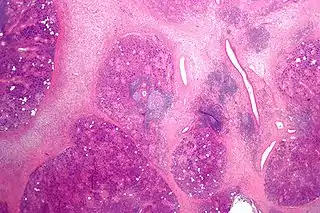

Micrografía de una sialadenitis crónica | ||